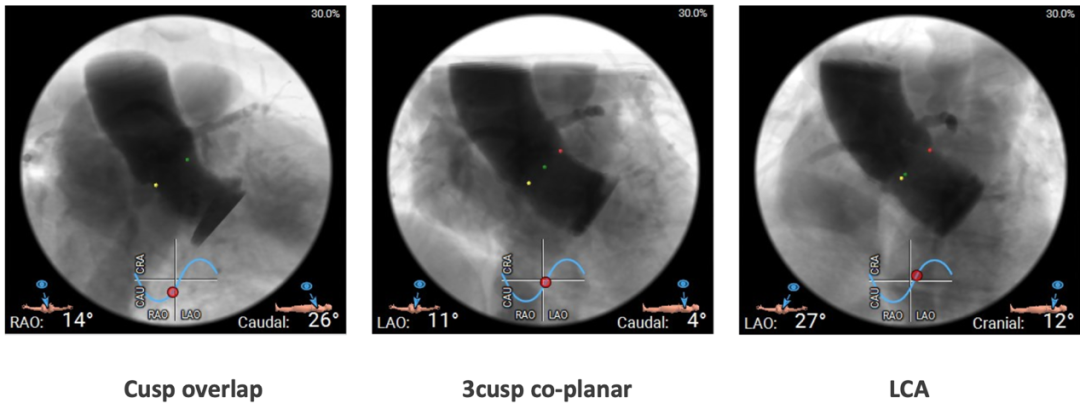

植入视图: